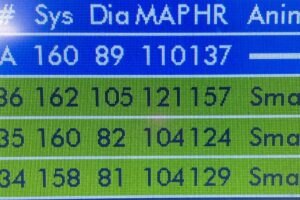

犬や猫の血圧測定について